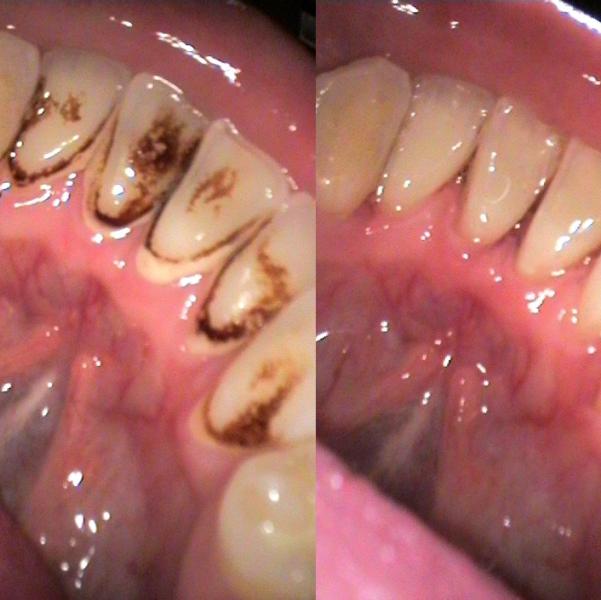

Приглашаю на ультразвуковую чистку зубов. Сейчас скидка 50%. Стоимость всего 500 рублей. А также все виды лечения и протезирования зубов. Консультация бесплатная.

@marina172, да, чистка ультразвуком и щетками всех зубов 500 руб. Следы от смол и никотина удаляю. Как правило достаточно 1 процедуры. Редко 2, если налет очень сильный. График работы и адрес чуть выше. Буду рада помочь.